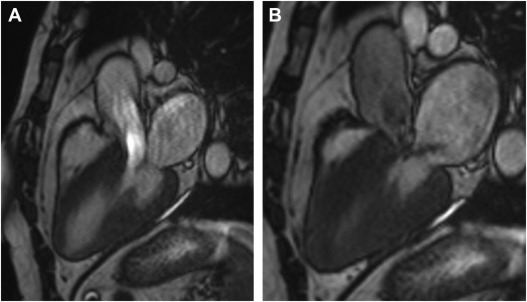

Added Value of Cardiovascular Magnetic Resonance in Primary Mitral Regurgitation.

Circulation. 137: 1361-1363Marrouche N.F. Wilber D. Hindricks G. et al.

Mitral regurgitation recovery and atrial reverse remodeling following pulmonary vein isolation procedure in patients with atrial fibrillation: A clinical observation proof-of-concept cardiac MRI study.

J Interv Card Electrophysiol. 37: 307-315Dell’Era G. Rondano E. Franchi E. et al.